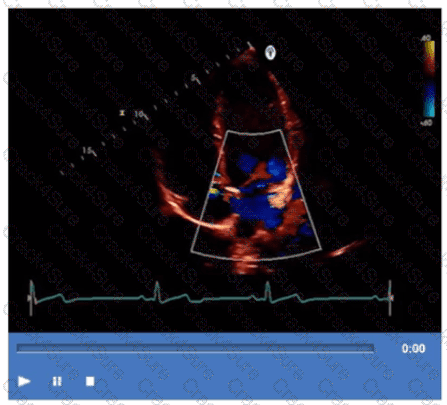

Which finding is demonstrated in this video?

What is the incidental finding seen by color Doppler in this four-chamber view of a patient with left atrial enlargement?